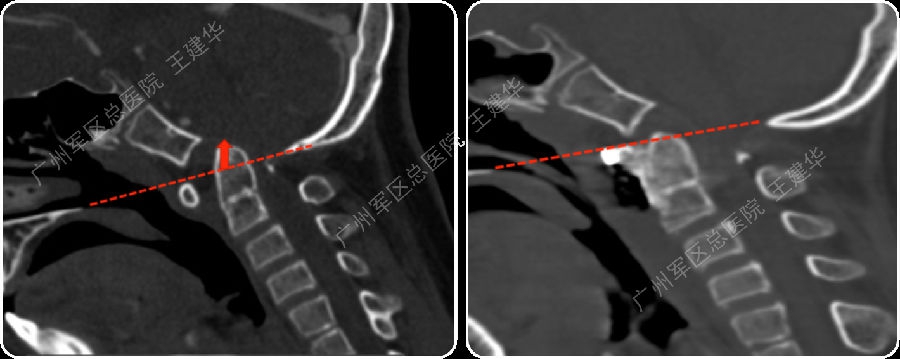

手术前后对比

可以看到:

陷入枕骨大孔的寰椎和齿突已经下拉复位,枕颈排列恢复正常

脑干压迫解除,延髓脊髓角恢复正常

手术后6年复查:

颅颈椎序列恢复正常并骨性融合